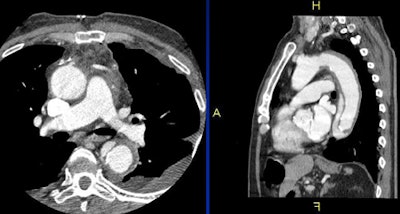

- Acute significance: pulmonary embolism (PE), aortic dissection

The locations of extracardiac findings on a typical cardiac CT scan include the aorta and the pulmonary arteries; lymphadenopathy in the mediastinal region; nodules in the lungs, pleura, and chest wall; and abdominal abnormalities, White said.

And it's true that unlike lung cancer screening subjects, patients undergoing coronary CTA are experiencing chest pain and are symptomatic. They have also been given contrast, and conditions such as pulmonary embolism or aortic dissection that would never be seen at noncontrast lung cancer screening can be identified on CTA. Lung screening subjects also tend to be older than cardiac CT patients.